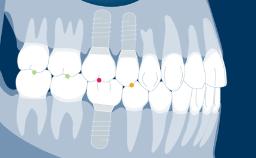

O projeto de todas as próteses sobre implante deve ser baseado em um plano protético e deve abordar todos os fatores de planejamento específicos identificados como relevantes. Há vários aspectos que são comuns ao planejamento da maioria das próteses fixas sobre implante (ou PFs), e é útil organizar esses pontos em uma sequência lógica de planejamento. O primeiro ponto é a seleção do tipo e configuração da PF. O próximo ponto é a seleção do método de retenção, seguido da consideração dos aspectos externos e da estrutura interna necessária para abordar fatores como estética, função e força. Este módulo examinará cada um desses pontos de planejamento, por sua vez. Os Módulos de Aprendizado da Academia, mais detalhados e separados, baseiam-se no presente Módulo e abordam a seleção de materiais restauradores para a PF, a seleção de pilares e a configuração dos implantes.

- selecionar o tipo de prótese e configuração das suas unidades